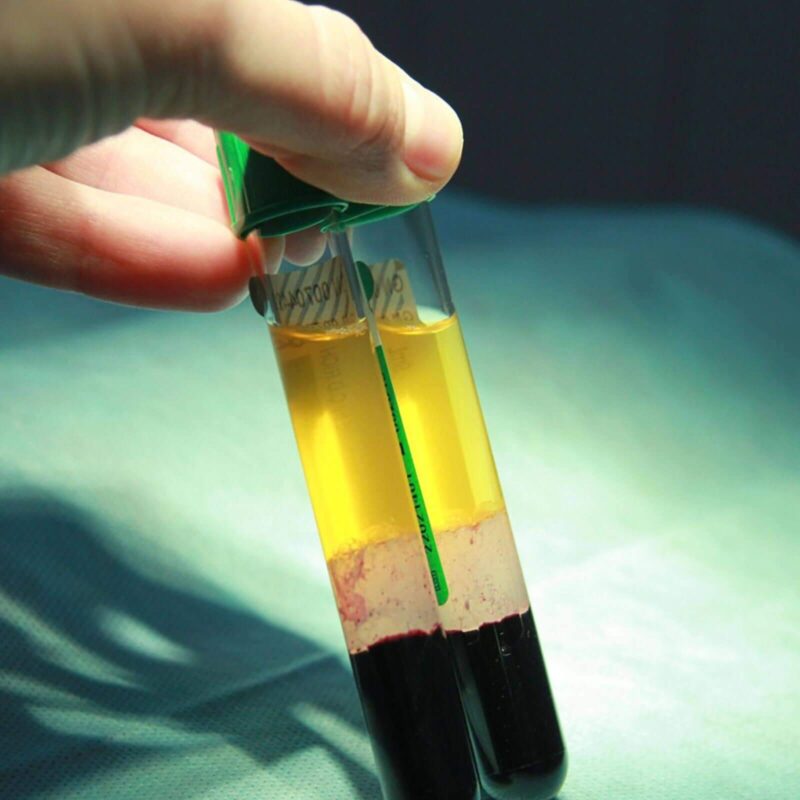

About Vampire Facial (Platelet Rich Plasma)

The Vampire Facial, also known as Platelet Rich Plasma (PRP) therapy, is a cosmetic skin rejuvenation procedure that utilises your own blood components. Microneedle injections of PRP stimulate natural healing and rejuvenation processes.

A small amount of blood is drawn and the platelet-rich plasma is prepared. PRP, containing growth factors, is strategically injected using microneedles.

This treatment promotes collagen production, improves skin texture, and enhances tone and radiance. It offers a non-surgical, natural approach to rejuvenation, harnessing the regenerative potential of your own blood.

Experience the transformative effects of the Vampire Facial for a revitalised and refreshed complexion.